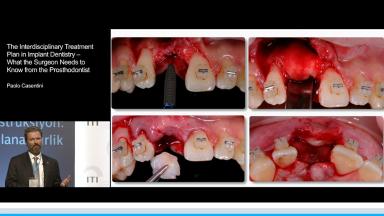

Part one of a two-part presentation gives a comprehensive overview of how to treat complex cases using an interdisciplinary approach in implant dentistry. From the prosthodontist’s point of view, the workflow starts with careful prosthetic planning by the use of wax-ups or set-ups, and in some cases orthodontic pretreatment is indicated. This lecture demonstrates how the prosthetic planning is then transferred by surgical templates to facilitate the correct 3D prosthodontically driven implant placement. In this workflow, the provisional prosthesis conditions the soft tissue in order to optimize esthetics prior to finalizing the prosthetic rehabilitation. This lecture includes a series of ‘Prosthetic Rules’ to serve as benchmarks for effective prosthodontically driven treatment.

- describe the workflow of careful prosthetic planning, surgical templates during implant placement, provisional prosthesis with soft tissue conditioning, and final rehabilitation